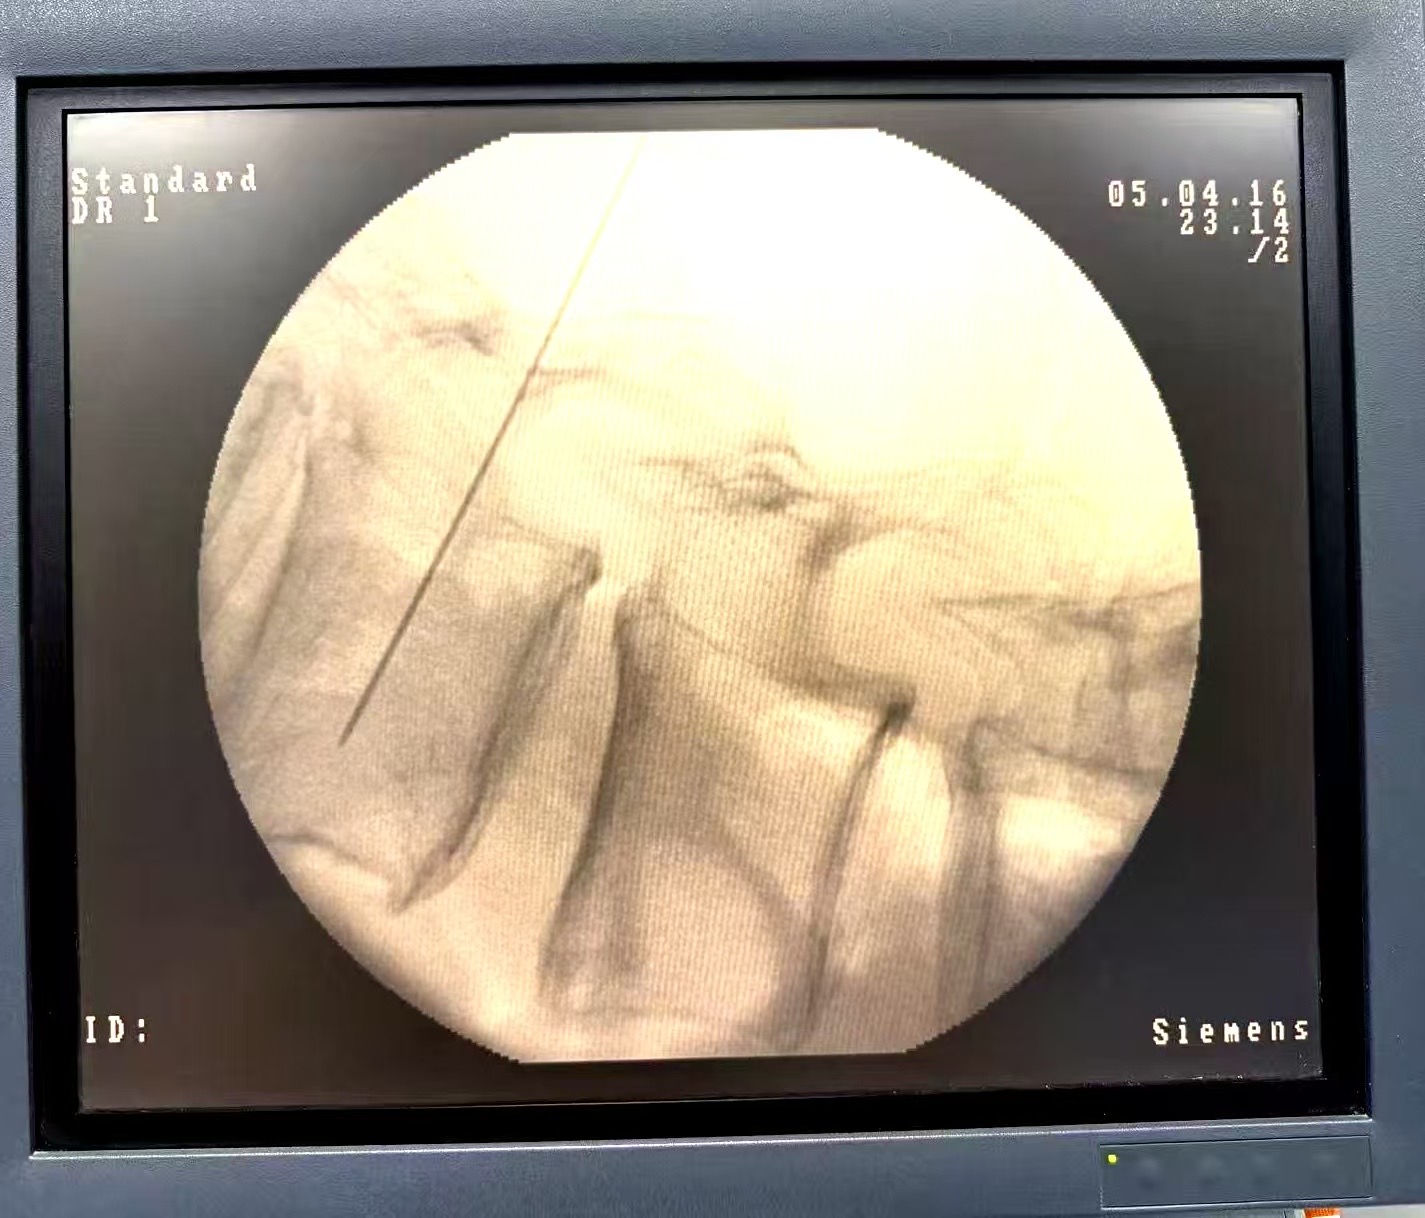

在接诊后,老年内二科在崔巍主任和石静教授的组织下对患者进行了全面评估并与疼痛科展开密切合作。经团队讨论,一方面通过规范药物调整尝试改善症状,并同时由疼痛科每晓鹏主任、申晓东教授、王诗雨医师组成的医疗团队为患者实施了经皮微创介入神经调控术。手术顺利,术后患者腹痛显著缓解,精神状态、进食与休息均有明显改善,生活质量得到实质性提升。